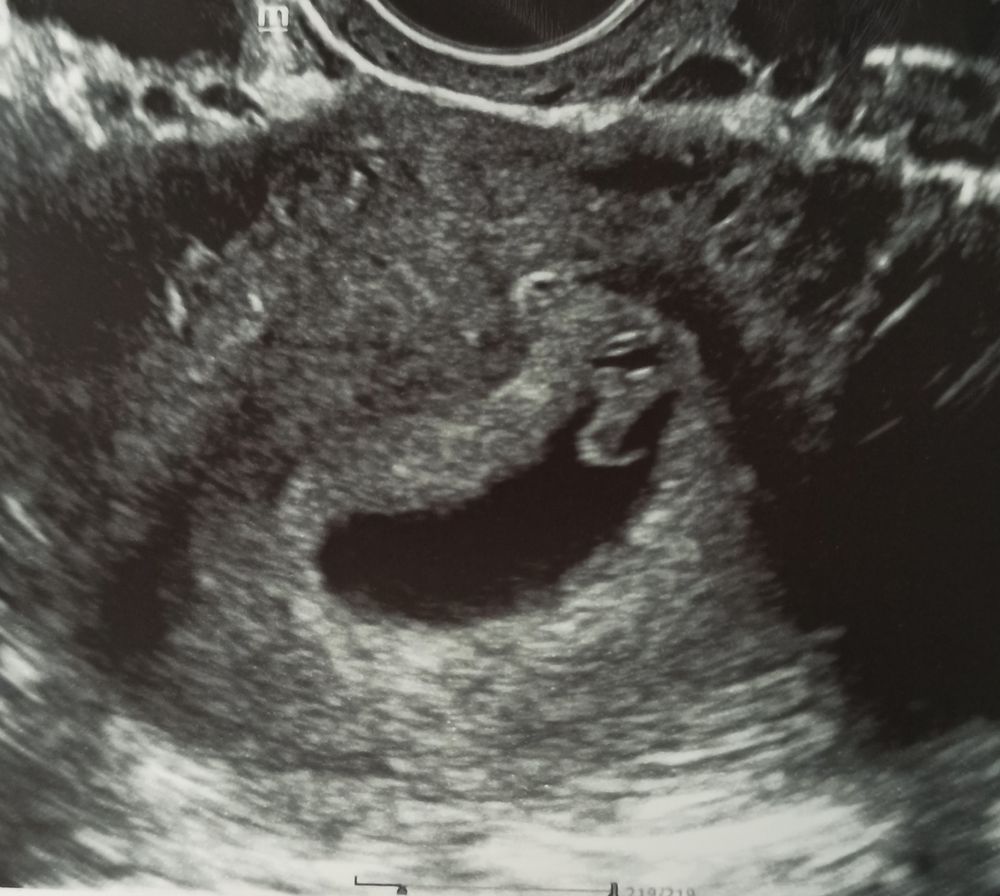

УЗИ на 34 дпо (6+6) ❤🤞🤞🤞

Сходили на УЗИ вместе с мужем, он счастлив🥰 сегодня 20 марта на 34 дпо (6+6):

ПЯ 25 мм, ЖМ 3 мм, КТР 9 мм, ЧСС 141 уд/мин, киста ЖТ 41*36 мм. Врач сказал, что прикрепление плаценты по передней стенке в центре в дне матки, так что не знаю как по методу Рамзи смотреть, по фото плацента сверху слева, может мальчик👦❤ это было бы здорово 👍 Позже сдам анализ на определение пола плода по крови матери. Токсикоз продолжается: тошнит от голода, после еды тяжесть и отрыжка, приходится есть каждые 2 часа понемногу, надеюсь ещё недельку и пройдëт, как и в другие беременности токсикоз был с 5 по 8 неделю, сейчас хочется мясное, острое, солёное, кислое, а вот на сладкое не тянет, может позже вернётся тяга к сладостям. Хотела посмотреть прогестерон и до кучи для архива сдала сегодня и ХГЧ: